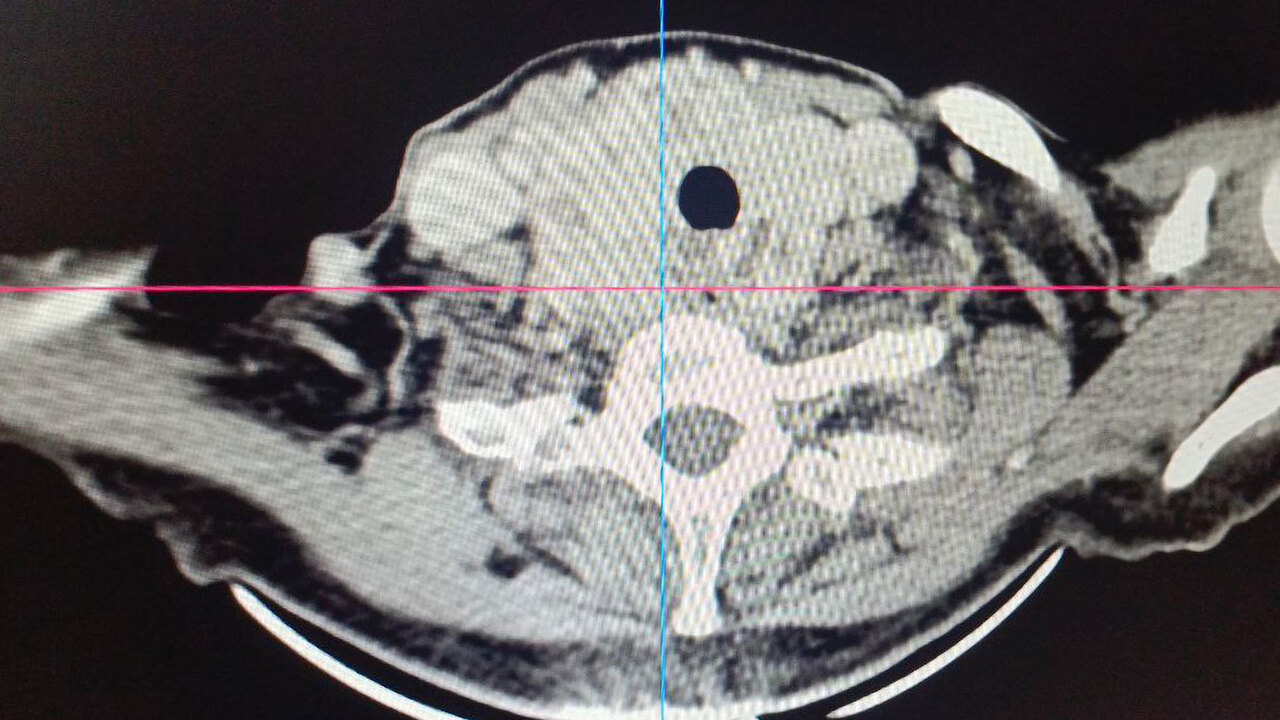

«Особенность случая — в аномальном расположении щитовидной железы, — пояснил профессор Игорь Макаров, заведующий кафедрой общей хирургии СамГМУ. — Зоб не просто увеличился, а опустился за грудину, сдавив трахею по типу «воротника» и вплотную подойдя к магистральным сосудам». Из-за этого женщина задыхалась даже при малейшей нагрузке, а хирурги всерьез рассматривали необходимость рассечения грудной клетки.